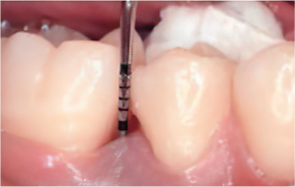

Emdogain Surgical Procedure

STEP 02

Scaling and Root Planing (SRP)

-

STEP 03

Removal of calculus and plaque